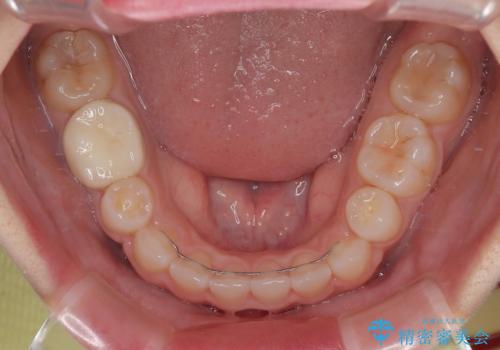

- 矯正装置

- メタルブラケット

- 治療計画

- 前歯のクロスバイトと口元の膨らんだ横顔の印象を気にして来院された患者様です。

レントゲン写真の分析結果からは、それほど口元が突出しているという結果にはなりませんでした。

しかしながら、唇を閉じたときに口元に緊張感があり、そのまま叢生を解消すると横顔が突出した印象になる可能性が高かったため、上下左右の小臼歯4本を抜歯して、ワイヤー装置にて矯正治療を行うこととしました。